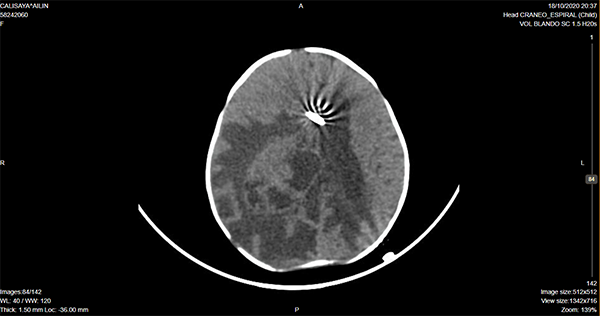

Caso ilustrativo n°4: Houkin tipo 4(Figura 4)

Paciente de 4 meses de vida, fue llevada a la guardia por vómitos intermitentes, posteriormente agregó sensorio alternante, tendencia al sueño. Al examen físico se evidenció perímetro cefálico aumentado, fontanela llena, estrabismo convergente ojo izquierdo intermitente y retraso de adquisición de pautas madurativas: no sigue objetos y sin sostén cefálico. Se realizaron múltiples punciones transfontanelares en otra institución y se derivó a nuestro centro. Ingresó en la madrugada y se realizó cirugía de colocación de drenaje ventricular al exterior. Posteriormente a las 12 hs presentó descompensación, con deterioro del sensorio. En imagen control por tomografía se evidenció ventrículo ipsilateral a lesión colapsado y herniación subfalcial, por lo que se realizó cirugía de urgencia de exploración y exéresis. Evolucionó favorablemente.

Se consideró Houkin tipo 4, ya que se podría haber evitado dicho deterioro si se operaba directamente el tumor.

Figura 4: Imagen por Tomografía Cerebral computada que muestra catéter en cavidad ventricular, con herniación subfalcial de la misma. Se observa diástasis global de suturas craneanas, edema cerebral y lesión ocupante de espacio sólido-quística intraventricular derecha.